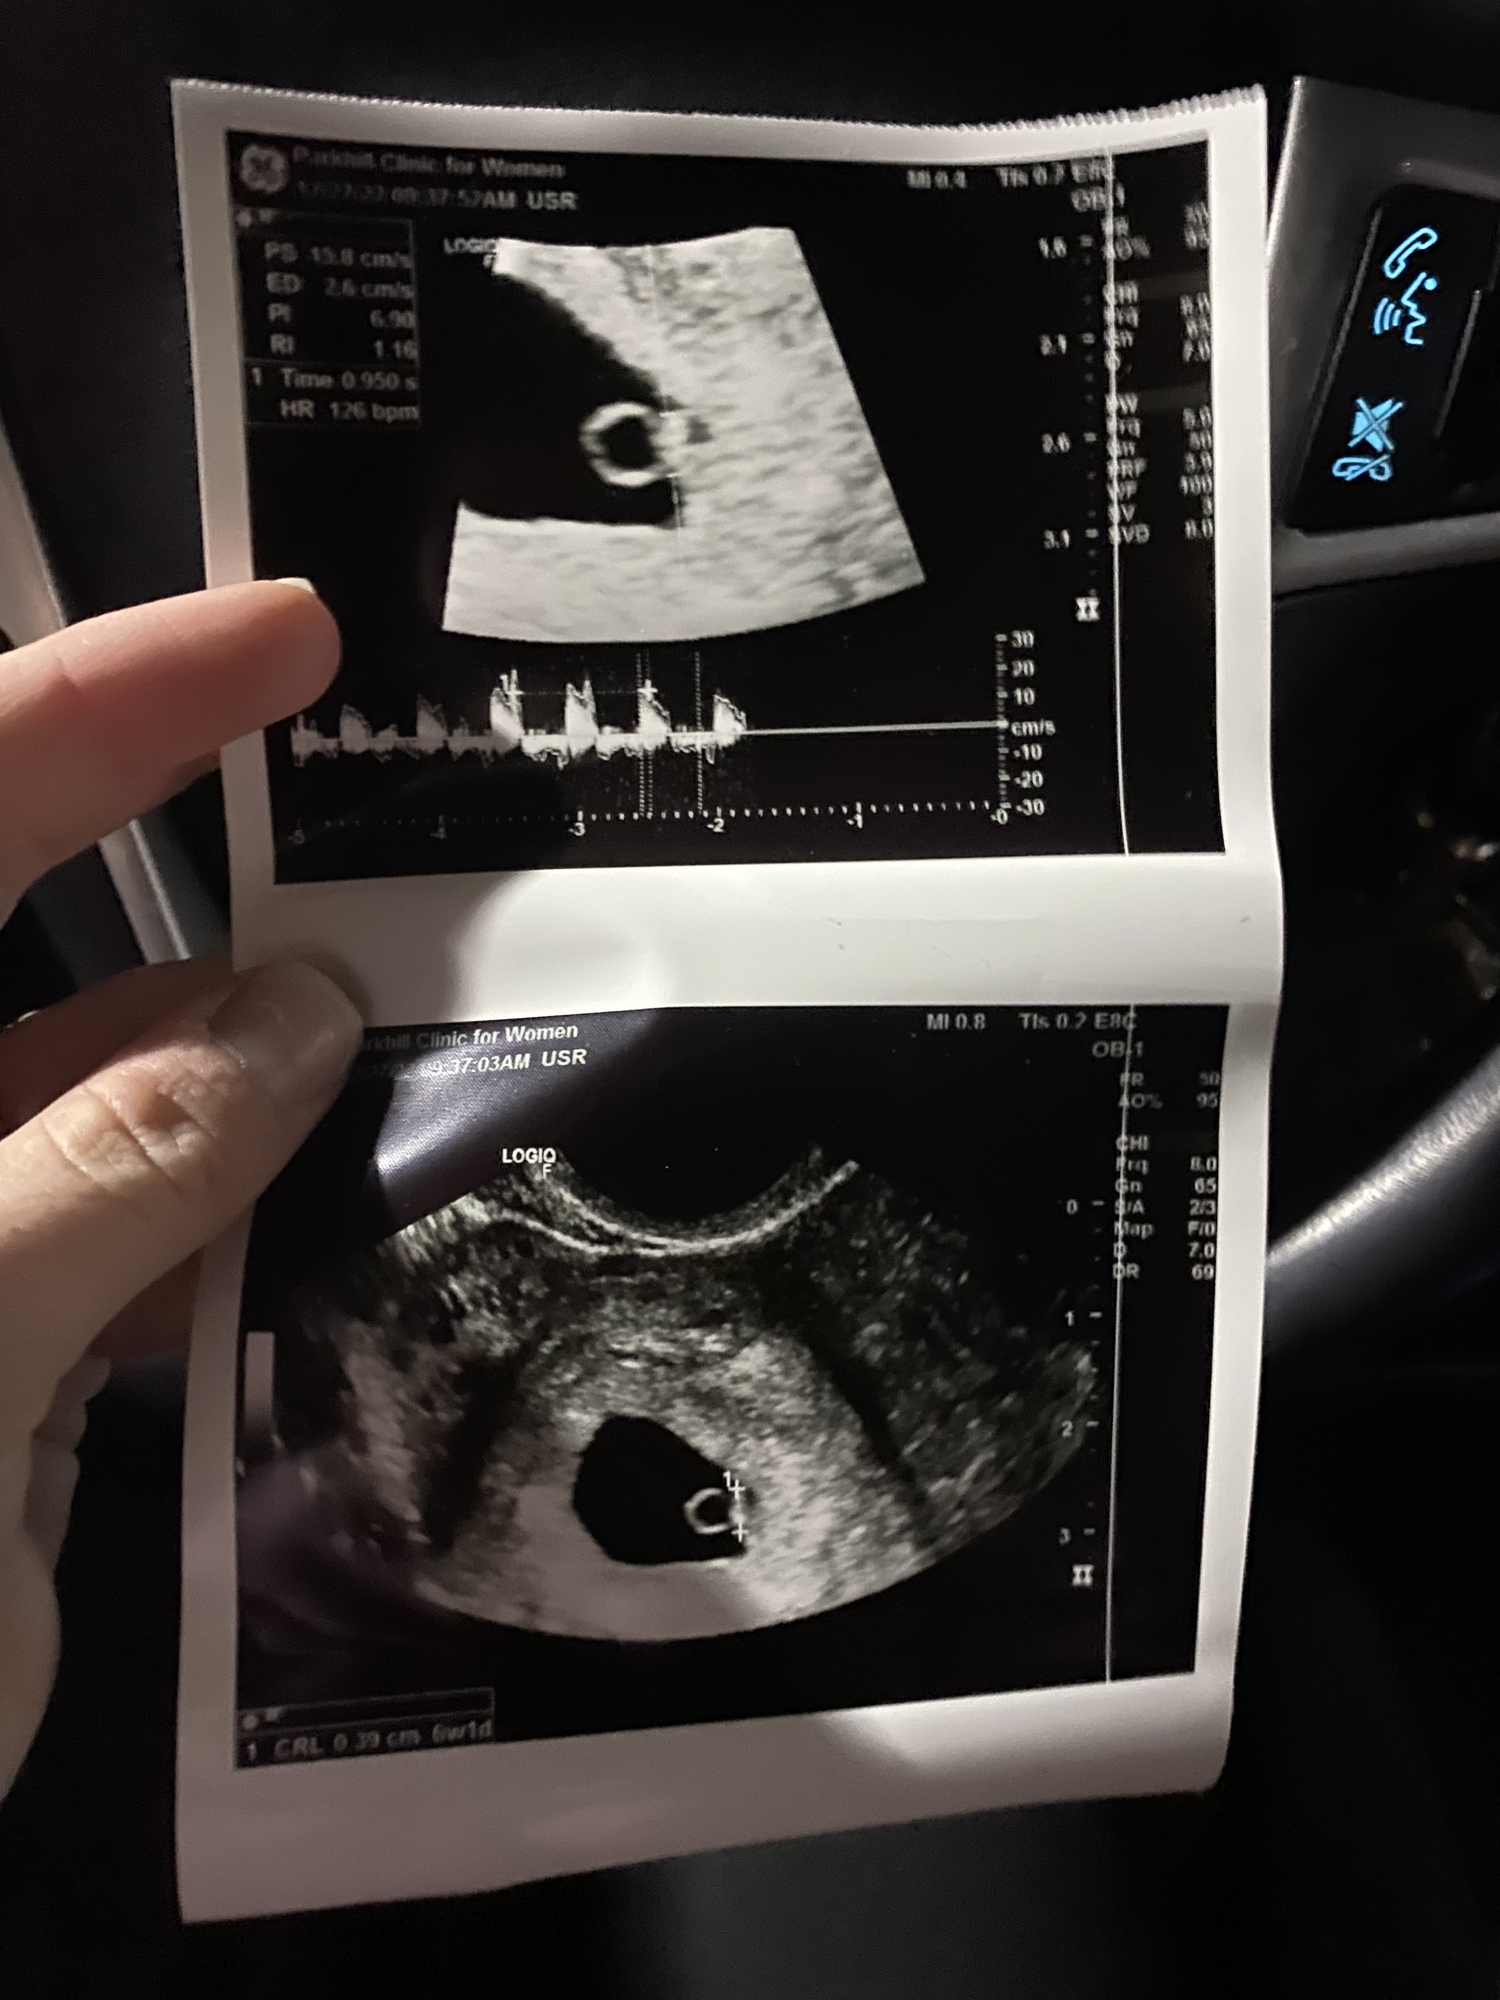

Just wanted to share two different ultrasound results in case it helps any of you. The doctor we saw for the first ultrasound came in right after and basically said we had a "slow" heartrate and could expect miscarriage. My research and instincts told me that was incorrect, and I pushed back. I had a blighted ovum last year, which was basically an empty sac at the same time (6 wks, 2 days) so seeing fetal pole and heartbeat seemed great to me! I was honestly shocked at the doctor's reaction.

The second doctor (we saw her today after the second ultrasound) told me it was irresponsible for them to flag anything over 100 at 6 weeks and that my first measurements were fine. It goes to show that there is variation among medical professionals, as well as different approaches, and on the earlier side, assuming certain elements are in place, it's ok to be optimistic!

SECOND ULTRASOUND Ultrasound date: 1/5/23 Gestational Age: 9 wks, 2 days Elements Present: Yolk sac, fetal pole, heartbeat CRL (crown rump length): 2.5cm Heart rate = 167 (per doctor, range should be 150-170) Due date = 8/8/23

For reference here are the previous ultrasound notes / measurements: Ultrasound date: 12/19/22 Gestational Age: 6 wks, 3 days Elements Present: Yolk sac, fetal pole, heartbeat CRL (crown rump length): .67 cm Heart Rate = 107 Due date = 8/10/23